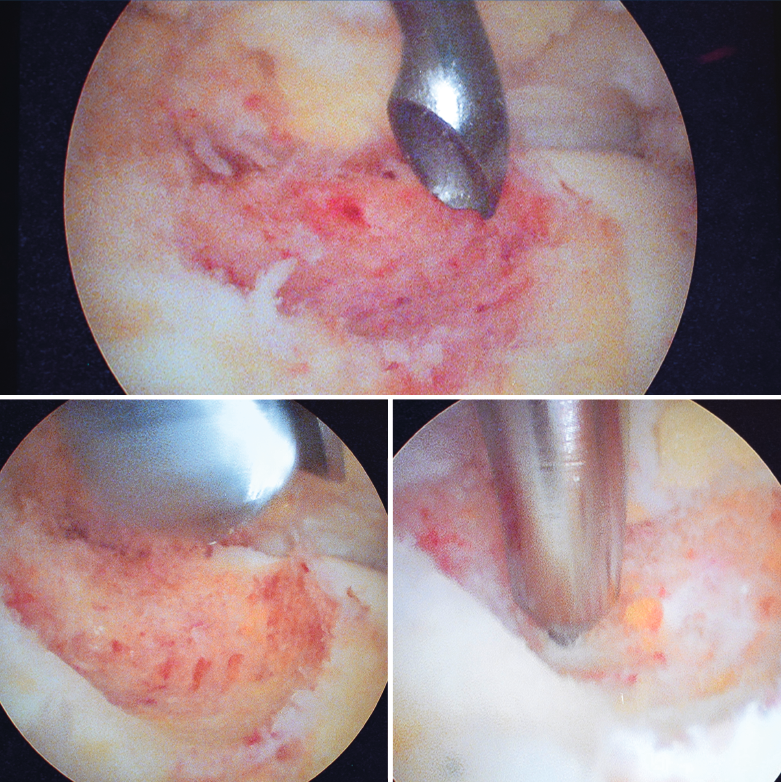

Se visualizó la cúpula astragalina y se observó a nivel del cuello del astrágalo anterointerno una tumoración rojiza con intensa reacción sinovial; se desbridó mediante un sinoviotomo de 4,5 mm (Stryker®, Kalamazoo, Michigan) (Figura 4), tras lo cual se comprobó la inestabilidad de la lesión que se desprendió en bloque (Figura 5), remitiéndose a estudio anatomopatológico.

Posteriormente se realiza curetaje del fondo, eliminando el hueso sobrante en los márgenes, hasta encontrarnos hueso esponjoso de aspecto macroscópico normal, y se realizan perforaciones mediante NanoFx® (Arthrosurface Inc., Bellingham, Massachusetts) (Figura 6).

Figura 4. Mediante los portales artroscópicos anteriores habituales (anteromedial y anterolateral) se observa a nivel del cuello del astrágalo anterointerno la característica tumoración de color rojo cereza, que se desbridó con sinoviotomo.

Figura 6. Curetaje del fondo de la lesión, visualizando hueso esponjoso de aspecto macroscópico normal. Finalmente se realizan nanoperforaciones.